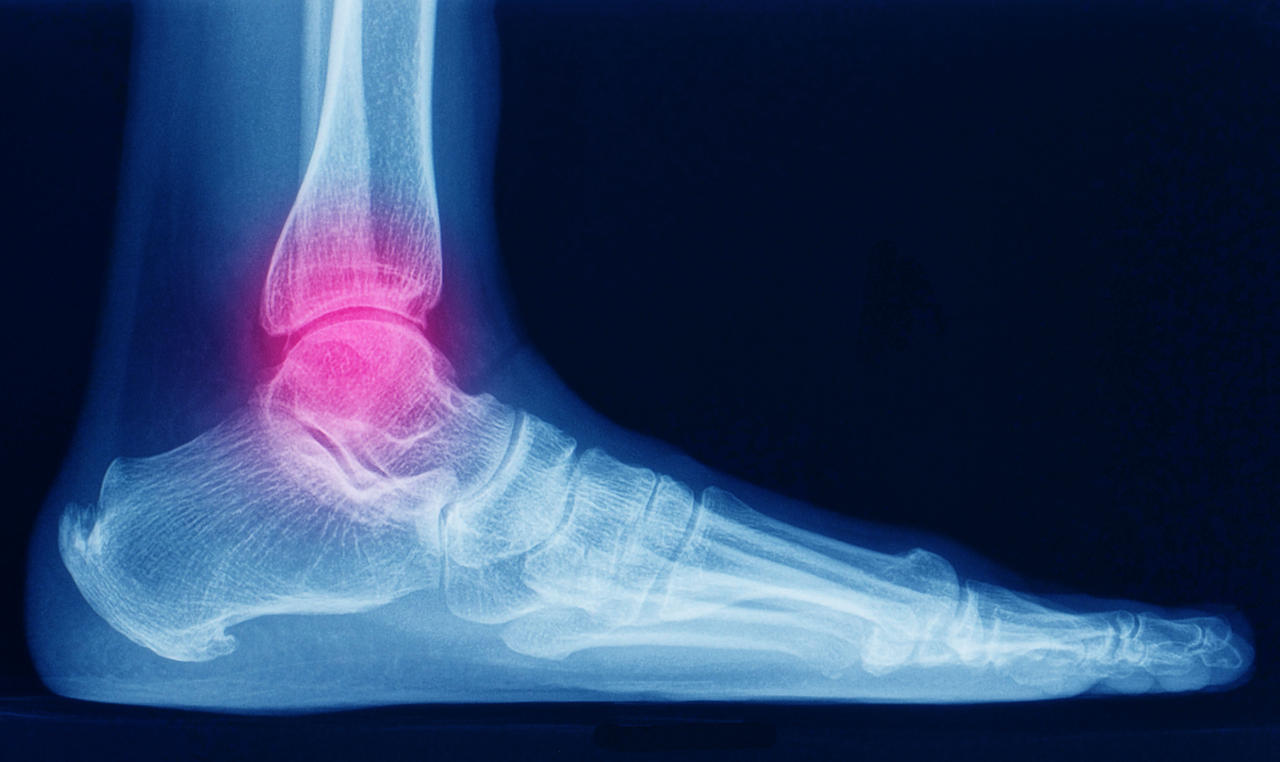

I distretti corporei maggiormente coinvolti sono: anche, colonna vertebrale, polsi, spalle e femore. Da notare che una frattura al femore, può condurre il soggetto colpito a una condizione di disabilità fisica.

Le sue conseguenze sono una diminuzione della densità minerale ossea e un aumento della fragilità e debolezza dell’apparato scheletrico con predisposizione alla comparsa di fratture al collo del femore, al femore, ai corpi vertebrali, all’avambraccio e alla parte prossimale vicino alla spalla per quanto concerne la frattura dell’omero.

Dove si riscontrano le fratture da osteoporosi

In tutto lo scheletro si possono riscontrare fratture da osteoporosi, ma quelle più frequenti sono:

- all’estremità prossimale del femore, in zona inguinale;

- all’estremità distale del radio, cioè al polso;

- sulle vertebre, lungo la colonna dorso lombare;

- all’estremità prossimale dell’omero, in zona ascellare;

- alle anche, intorno al bacino.